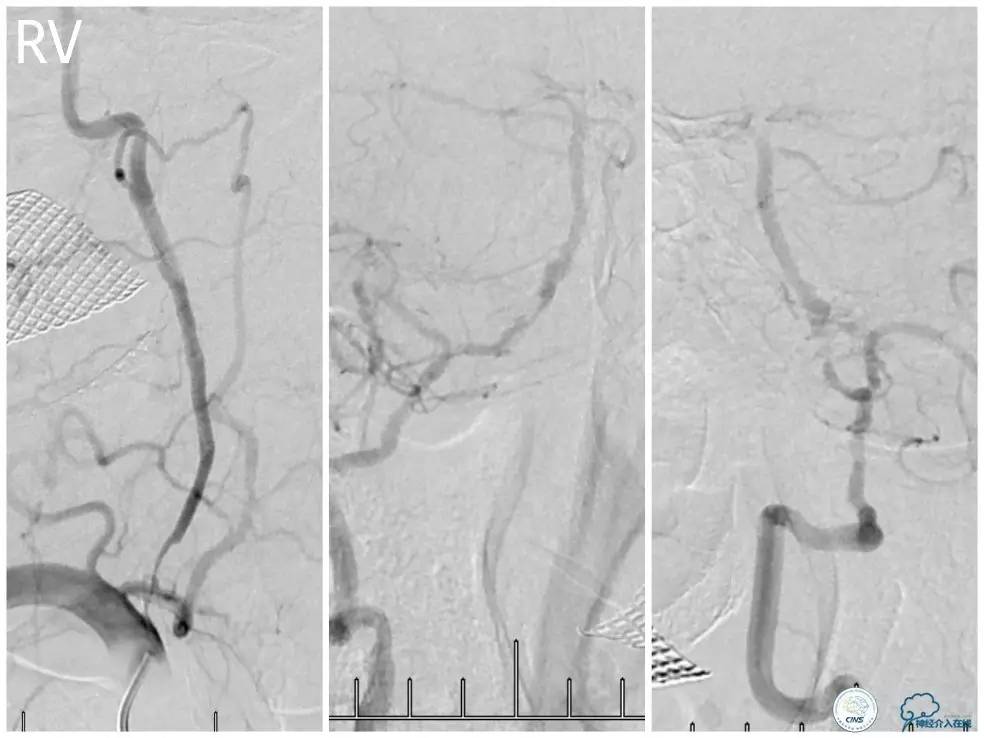

遂再次将Transend微导丝送至右大脑后动脉P1段,使用Gateway球囊(2.0mm×15mm)于支架最狭窄处后扩张(图15)。

图15

其后造影显示支架贴壁良好,远端血管显影好,前向血流TICI3级(图16)。

图16

缓慢回撤6F导引导管至锁骨下动脉,造影显示右椎V1段支架无移位,前向血流正常(图17)。

图17